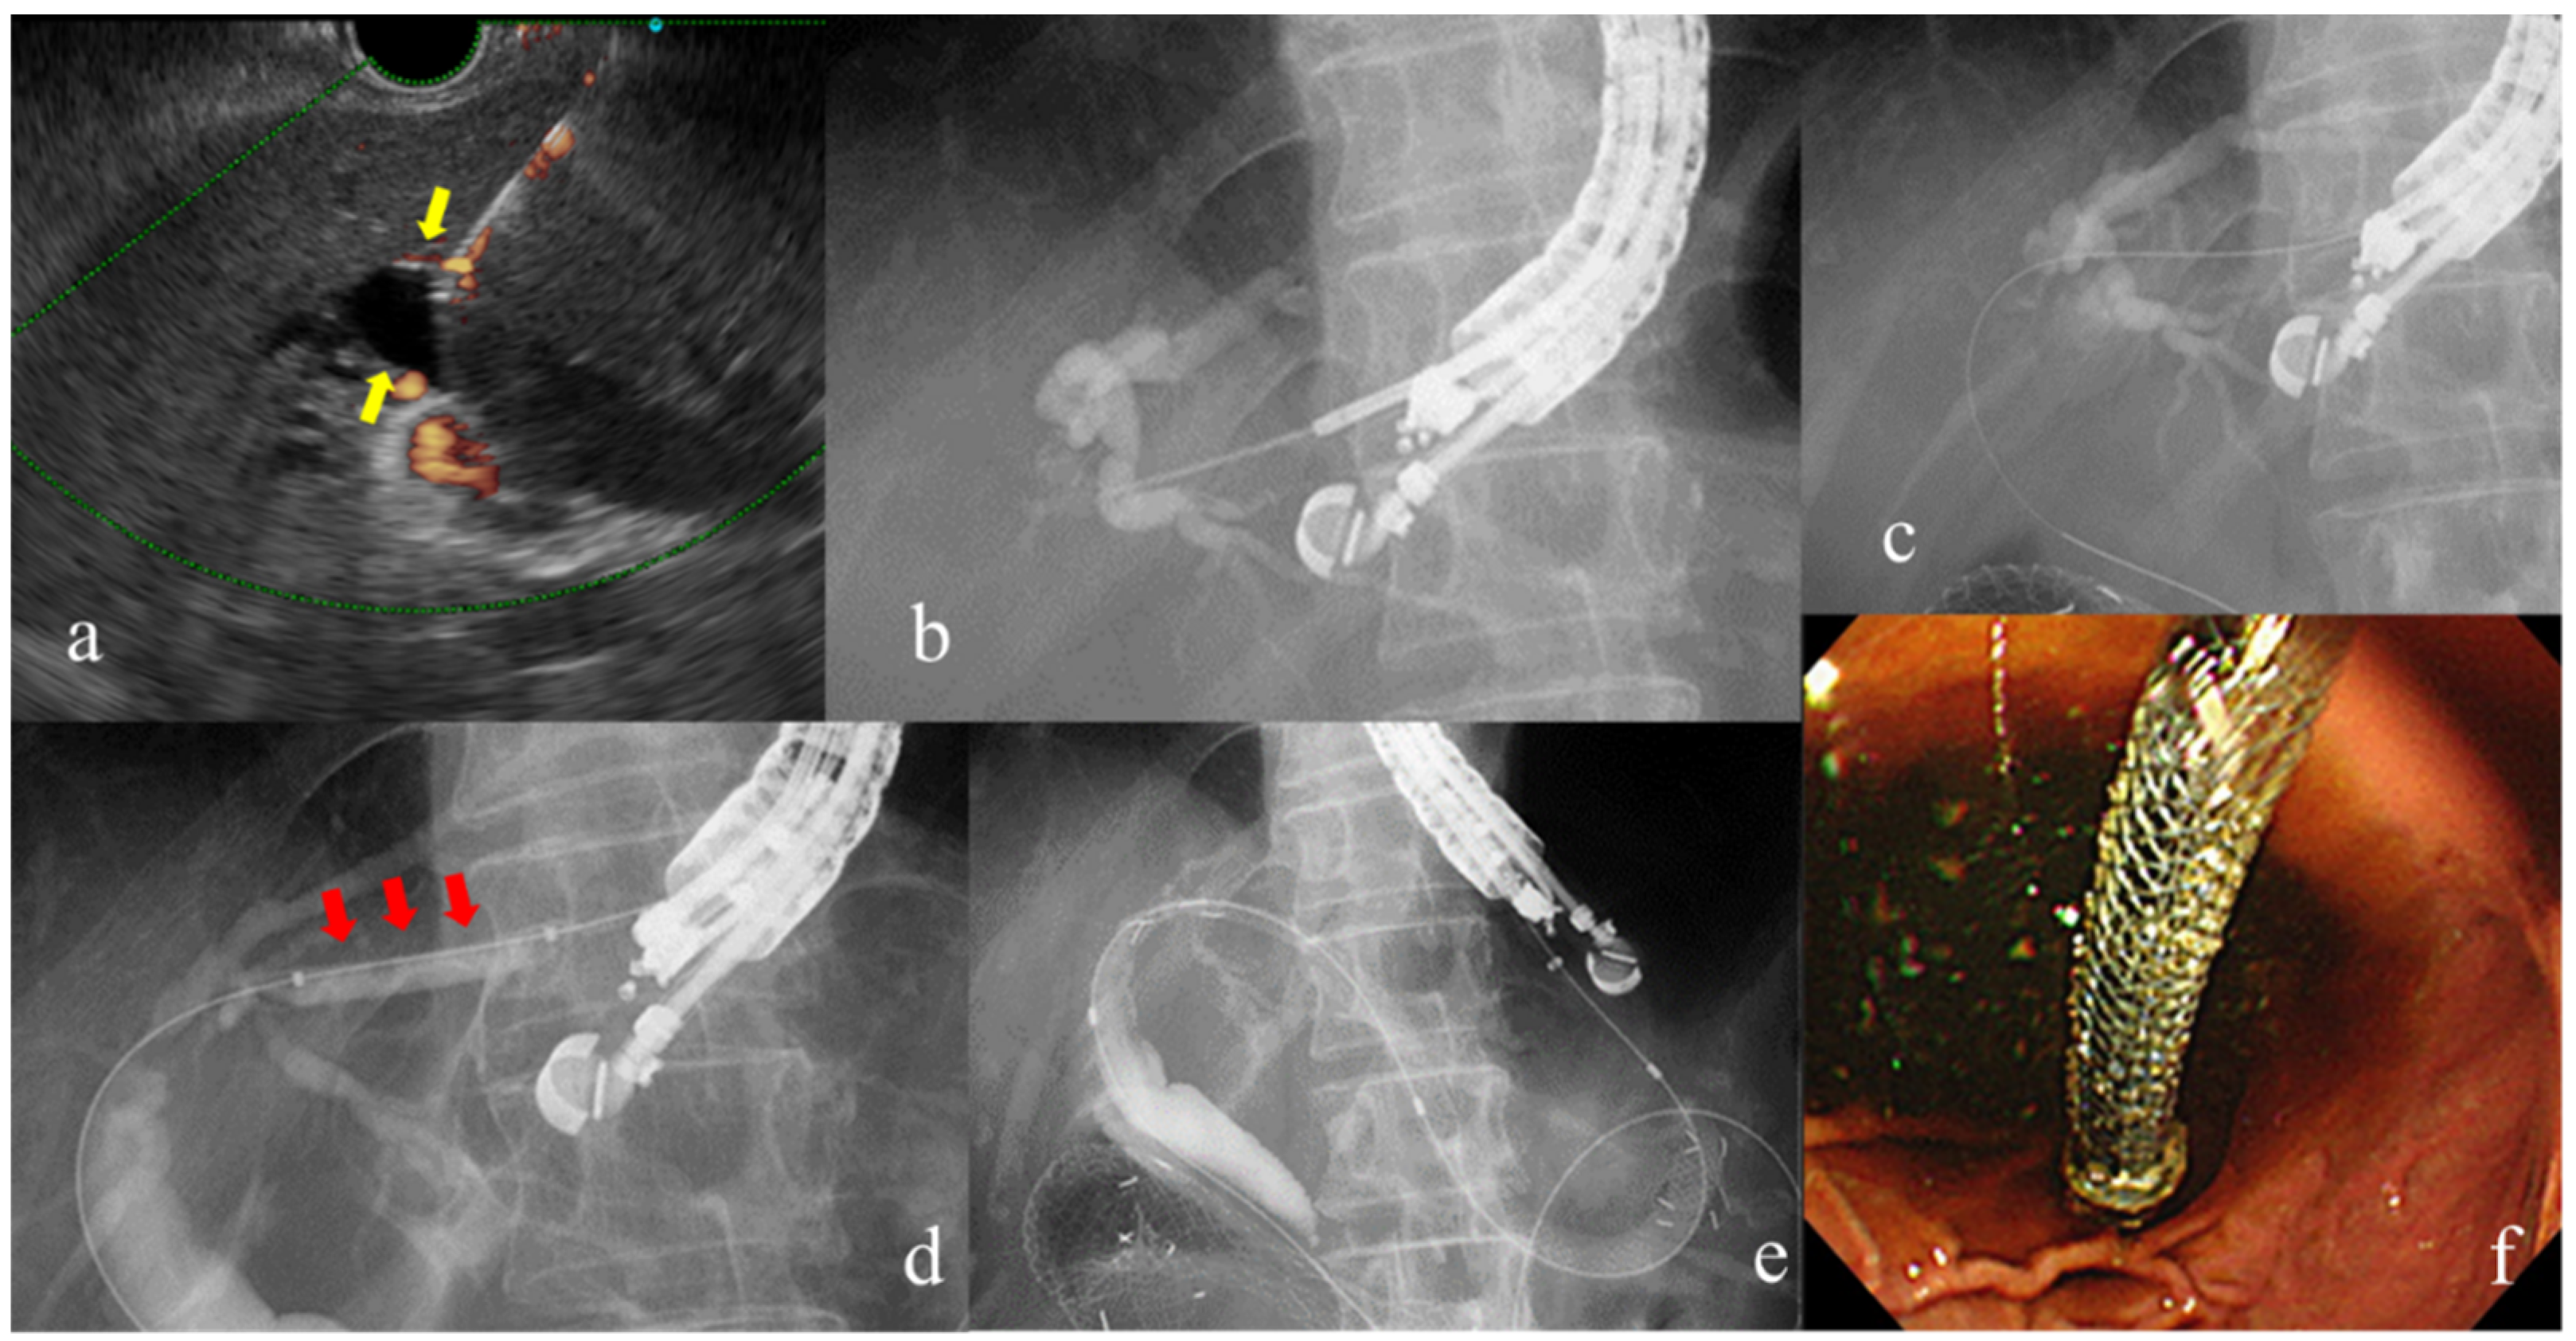

The procedure for EUS-BD is as follows. First, the bile duct is visualized using EUS from the gastrointestinal tract. Then, Doppler imaging is used to avoid blood vessels along the puncture line and the bile duct is punctured and a guidewire inserted. After confirming intraductal placement with a contrast tube, the fistula is dilated using dilation devices. Finally, a stent is placed [Figure 7]. The advantage of EUS-BD is its ability to achieve internal fistulization. However, there are potential drawbacks, including serious adverse events such as bile leakage, bile peritonitis, bleeding, and stent migration. The overall frequency of adverse events was reported to be 13.7%, with bile leakage at 2.2%, bleeding at 0.9%, and stent migration at 1.7% [79].

Figure 7. Procedure for EUS-guided hepaticogastrostomy: (a) The dilated intrahepatic bile duct depicted by EUS (yellow arrow shows). (b)Puncture by EUS-FNA needle and cholangiography of the intrahepatic bile ducts using contrast agent. (c)Insertion of the guidewire through the needle. (d) Dilation of the puncture line. (e, f) Placement of the self-expandable metal stent.